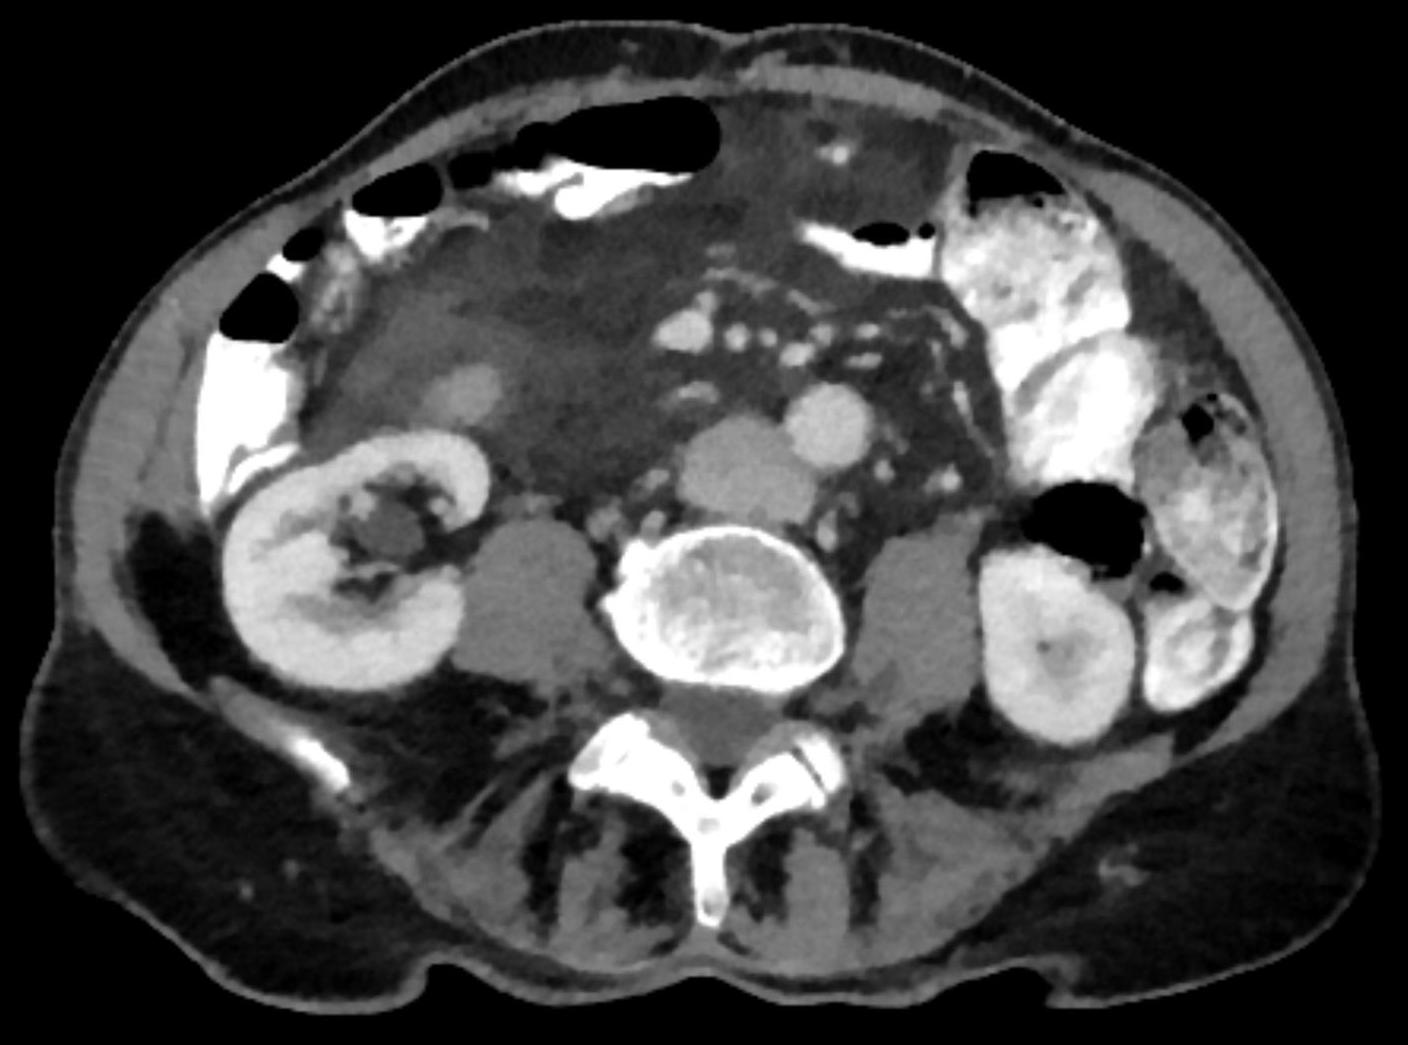

Os exames de tomografia computorizada permitem que as indurações de tecido adiposo fibroso inflamatório sejam bem delineadas [2]. Mesmo nos exames nativos, a densificação do tecido conjuntivo pode ser detectada no tecido adiposo, que apresenta um aumento de densidade nos exames com contraste. O contraste intravenoso é necessário para a deteção da síndrome de congestão venosa.

Imagem da capa: Paniculite mesenterial (suspeita); © hellerhoff, wikimedia